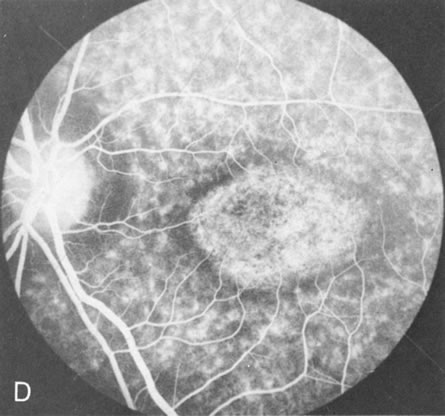

In the early stages of choroideremia, before choroidal atrophy is funduscopically obvious and when the picture resembles RP, FA indicates diffuse choroidal atrophy throughout the entire retina. Only the macular area remains preserved (Fig. 4A and B).

Fig. 4. Choroideremia and choroideremia carrier. A. The choroidal atrophy in this affected male is not apparent in the fundus. B. However, the angiogram shows diffuse atrophy of the choriocapillaris with persistent visualization of the larger choroidal vessels. C. This carrier female has peripapillary choroidal atrophy and diffuse pigment mottling. D. The patchy areas of focal choroidal atrophy that occasionally occurs in carriers is evident on angiography.

The typical carrier female, with focal or diffuse pigment mottling, does not show choroidal atrophy. However, a few carrier females have a more severe form with focal areas of choroidal atrophy. The presence of these areas, and possible progression, can be documented by FA (Fig. 4C and D). These carriers exhibit a mosaicism, which is explained by the Lyon hypothesis of random X-chromosome inactivation.